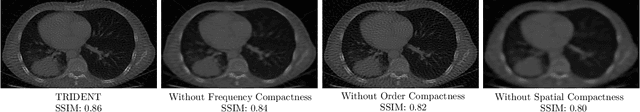

Abstract:Implicit neural representations (INRs) have garnered significant interest recently for their ability to model complex, high-dimensional data without explicit parameterisation. In this work, we introduce TRIDENT, a novel function for implicit neural representations characterised by a trilogy of nonlinearities. Firstly, it is designed to represent high-order features through order compactness. Secondly, TRIDENT efficiently captures frequency information, a feature called frequency compactness. Thirdly, it has the capability to represent signals or images such that most of its energy is concentrated in a limited spatial region, denoting spatial compactness. We demonstrated through extensive experiments on various inverse problems that our proposed function outperforms existing implicit neural representation functions.